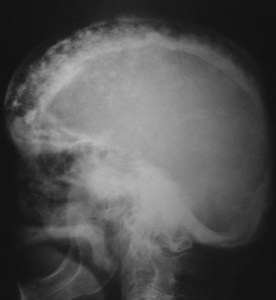

SIGNO DEL BRONCE BATIDO

El nombre de cráneo en bronce batido (o también cobre batido) hace referencia al aspecto de los huesos craneales con marcado aumento del patrón de circunvoluciones. La causa está en el aumento de la presión intracraneal que puede ser debido al cierre precoz de las suturas (craneosinostosis), hidrocefalia obstructiva, masas intracraneales o hipofosfatasia.

Afortunadamente, este signo es difícil de ver en la actualidad.

La imagen está cedida por el Dr. Leonard E Swischuk, quien ha otorgado el permiso para su publicación en esta web. Mi agradecimiento por su amabilidad.

Este otro caso, reciente, me lo ha enviado mi compañera la Dra. Irene Bocanegra, del H. Materno-Infantil de Málaga. Muchas gracias por su aportación.